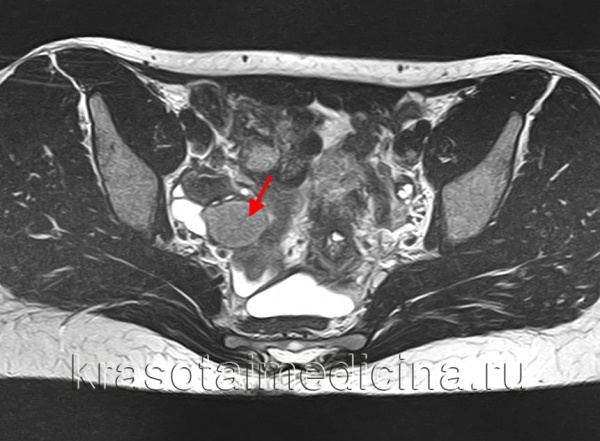

4. МРТ при функциональной кисте яичника:

• В зависимости от наличия ассоциированного кровоизлияния визуализационная картина сильно варьирует